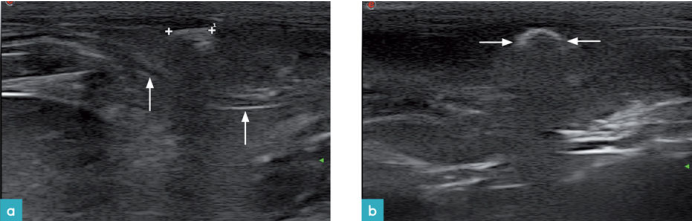

体表淋巴结病变表现为淋巴结的大小,回声,质地发生改变。肿瘤和淋巴结反应性病变都会导致淋巴结增大(尤其是增厚),淋巴结比正常形态更加偏圆,轮廓不规则,回声降低且质地不均匀,还可能在淋巴结内发现囊状区域(图20.图21)。所以需要通过活检或细针穿刺确诊病因。